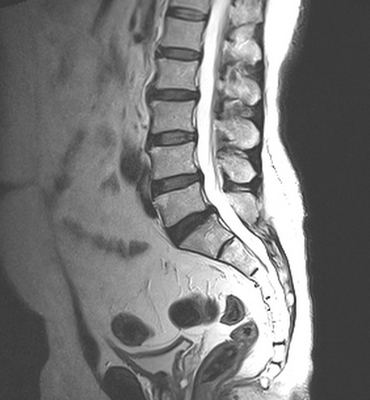

Сагиттальный срез позвоночного столба при МР-сканировании для оценки глубины поясничного лордоза

В каждом клиническом случае оптимальный вариант обследования определяет врач. Для диагностики деформаций позвоночного столба рентгена вполне достаточно, однако для более глубокого понимания проблемы могут потребоваться дополнительные сведения.

Магнитно-резонансная томография и рентгенография не заменяют друг друга. На обычных снимках с использованием Х-лучей нельзя выявить грыжи и патологии нервов. По результатам рентгенографии можно установить только косвенные признаки крупной и прогрессирующей опухоли. Магнитно-резонансная томография четко показывает подобные процессы, позволяет оценить степень их распространения и влияния на спинной мозг и на организм в целом.

Рентген важен для быстрого выявления искривления позвоночного столба. Результаты МРТ при сколиозе незаменимы для выбора тактики лечения пациента.